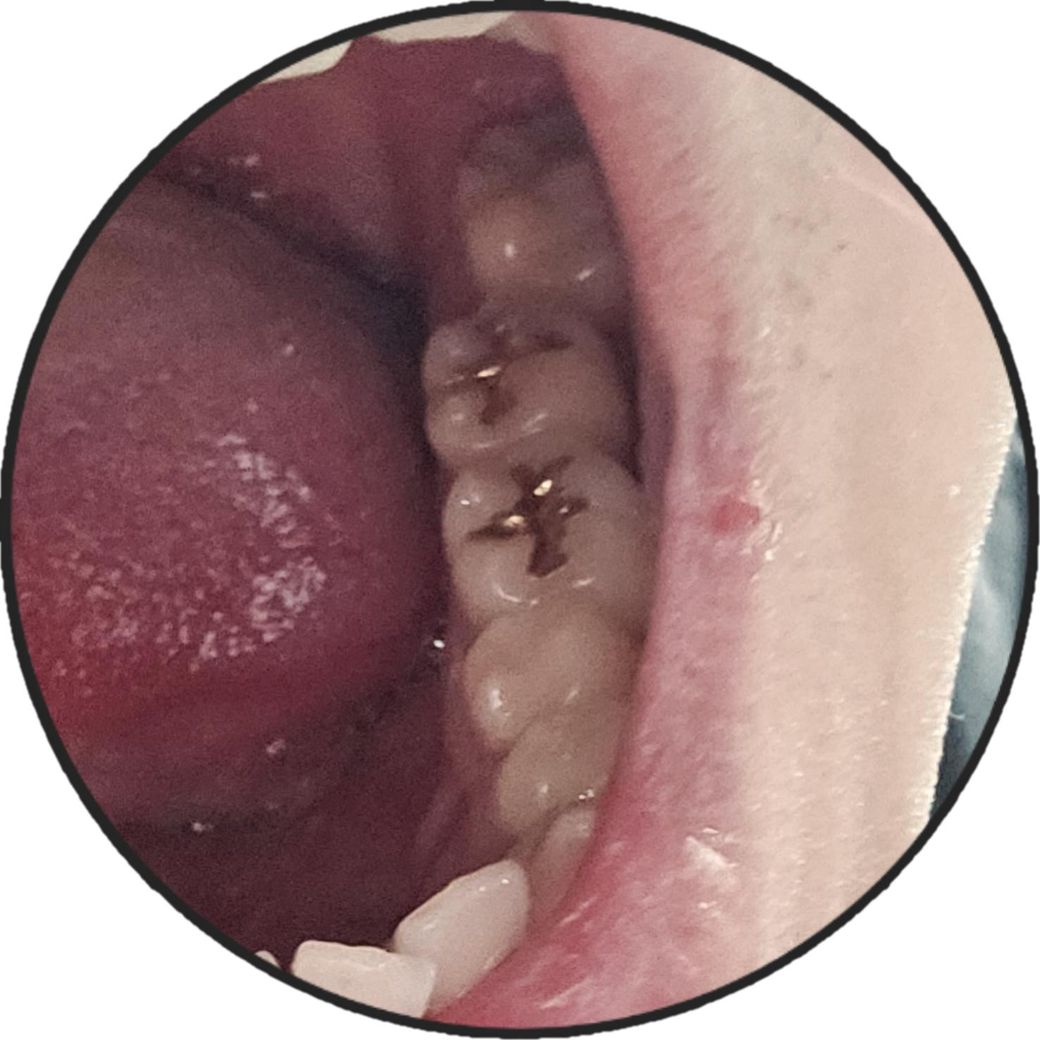

사랑니 발치방식 좀 봐주세요 쌤님들 .

하악 사랑니가 사진처럼 사이즈가 좀 큽니다

저런거도 절개하지 않고 통으로 발치할 수 있나요?

그리고 앞어금니랑 들러붙진 않은데 간격이 꽤 촘촘한데 발치시 앞어금니에 영향이 가진 않나요?

-> 네 치관 전부 노출되어있으면 절개안합니다

-> 가능성 낮습니다

구강악전문의를 찾아가는게 훨씬 쉽고 안전하게 발치하는건가요? 정상맹출이라도 치근이나 치관을 보고 의사에 판단에 따라 구강악전문의를 선택하는게 좋은건지 이정도의 맹출사랑니는 치과의사라면 다 가볍게 뽑으시는지 -> 큰 차이 없습니다

사진으로 보이는 사랑니는 발치를 하는데 크게 어렵지 않을 것으로 보입니다. 뿌리가 휘어 있는것이 아니면 쉽게 나올것으로 생각됩니다.